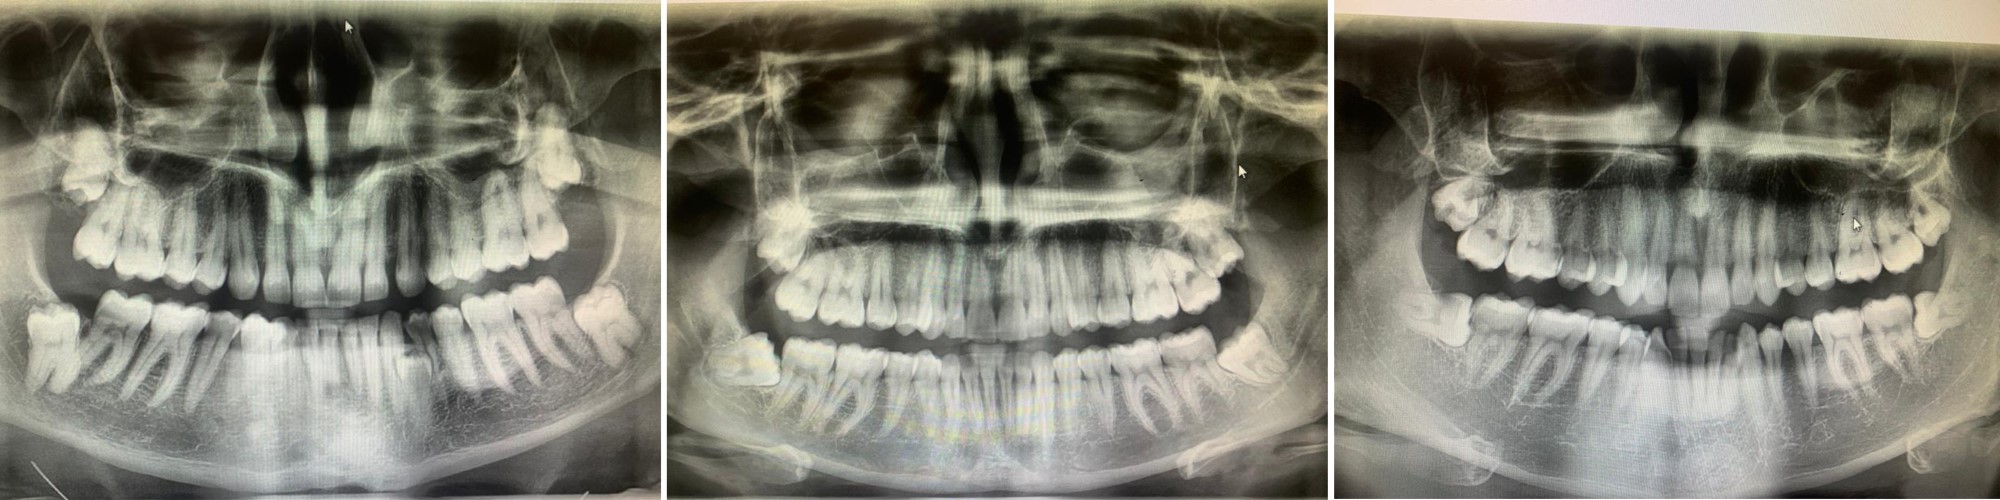

Alcuni esempi di denti del giudizio inclusi o in disodontiasi rimossi chirurgicamente